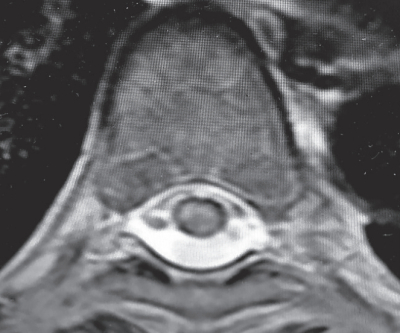

血液所見、血液生化学所見に異常を認めない。脳脊髄液所見は細胞数 69(多核球 60、単核球 9)/mm3(基準 0~2)、蛋白 62 mg/dL(基準 15~45)、糖62mg/dL。胸椎MRIのT2強調矢状断像と病変部の水平断像を別に示す。